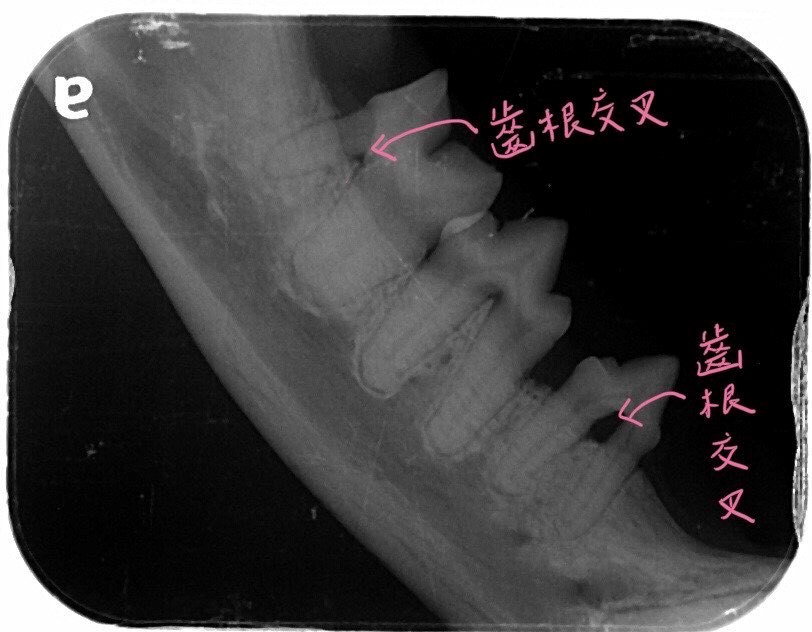

但在麻醉下拍攝牙科X光立馬發現本來看起來沒這麼嚴重的下顎第一臼齒與第三前臼齒骨頭已退縮,兩個牙齒中間的洞洞(也就是齒根交叉)都露出來可以被探針穿過,已經是嚴重牙周病的狀態